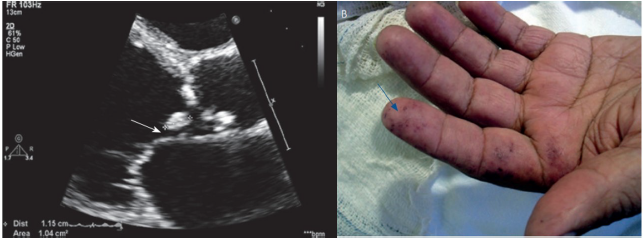

Paciente de 38 anos apresenta quadro de perda ponderal, febre de até 38,2° C, calafrios, queda do estado geral e lesões cutâneas não dolorosas em pés e mãos, com início há duas semanas. Refere ter valvopatia reumática e estar aguardando cirurgia na fila de hospital universitário de referência há mais de um ano. Ao exame: regular estado geral, FC 98 bpm, PA 112 x 70 mmHg, RCR 2T, bulhas normofonéticas com sopro sistólico 3+/6+ e diastólico 2+/6+ em foco aórtico, ausculta pulmonar sem alterações. Realizou a coleta de 3 pares de hemoculturas. Ecocardiograma do caso e lesões de pele reproduzidas abaixo.